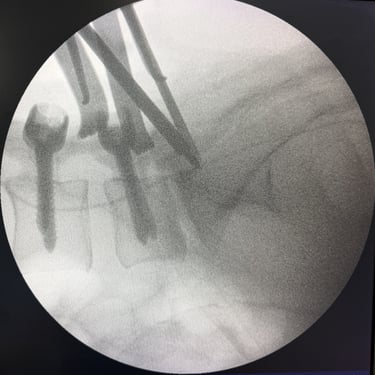

Manejo quirúrgico de la hernia lumbar con inestabilidad: enfoque moderno con FTP y TLIF

La hernia lumbar con inestabilidad vertebral es una patología frecuente que causa dolor lumbar persistente, ciática y limitación funcional, afectando la calidad de vida del paciente. Cuando el tratamiento conservador no logra resultados adecuados, la cirugía se convierte en la mejor opción terapéutica. La fijación transpedicular con tornillos (FTP) junto con la técnica TLIF (Transforaminal Lumbar Interbody Fusion) permite estabilizar la columna, descomprimir las estructuras nerviosas y lograr una adecuada fusión ósea. Este abordaje, especialmente mediante técnicas mínimamente invasivas (MISS), ofrece múltiples beneficios, como menor daño muscular, menor dolor postoperatorio y recuperación más rápida, facilitando el retorno temprano a las actividades cotidianas con mejores resultados clínicos.